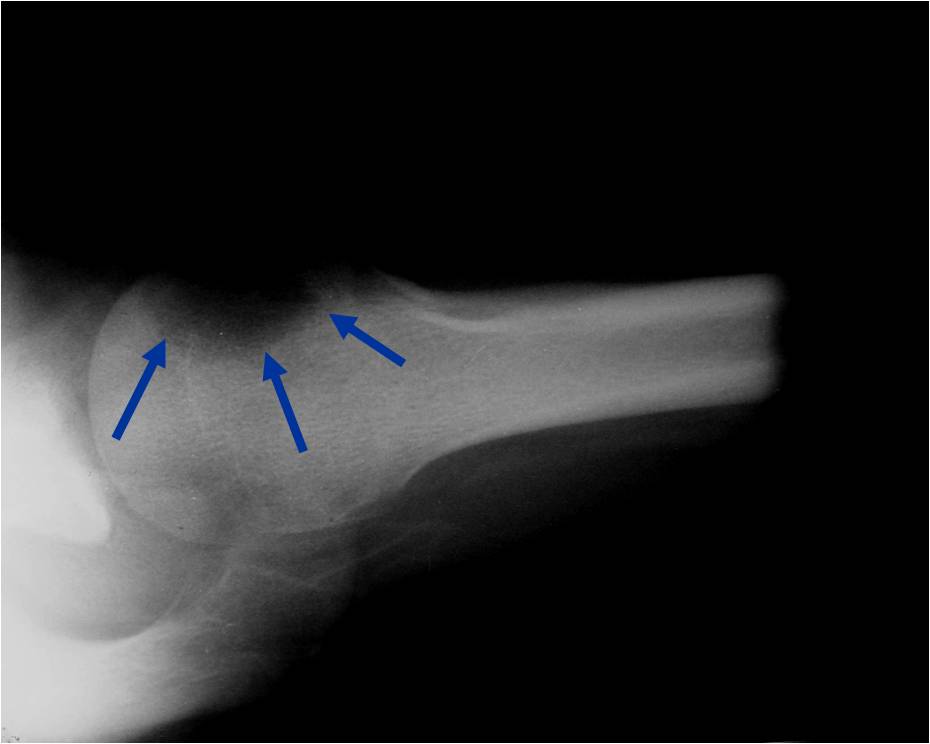

- (CT appearance)

- Most useful for detecting subtle mineralization not apparent on X-rays

- Useful for identifying intact periosteum around any expansile soft tissue component

- surrounding thin reactive shell of bone/mineralization (Egg Shell Rim of Calcification)

- helps place the tumor in a benign category

- helps evaluate:

- bony quality

- extent of bone and cortical destruction

- whether the subchondral plate of bone adjacent to the articular cartilage has been destroyed or is intact